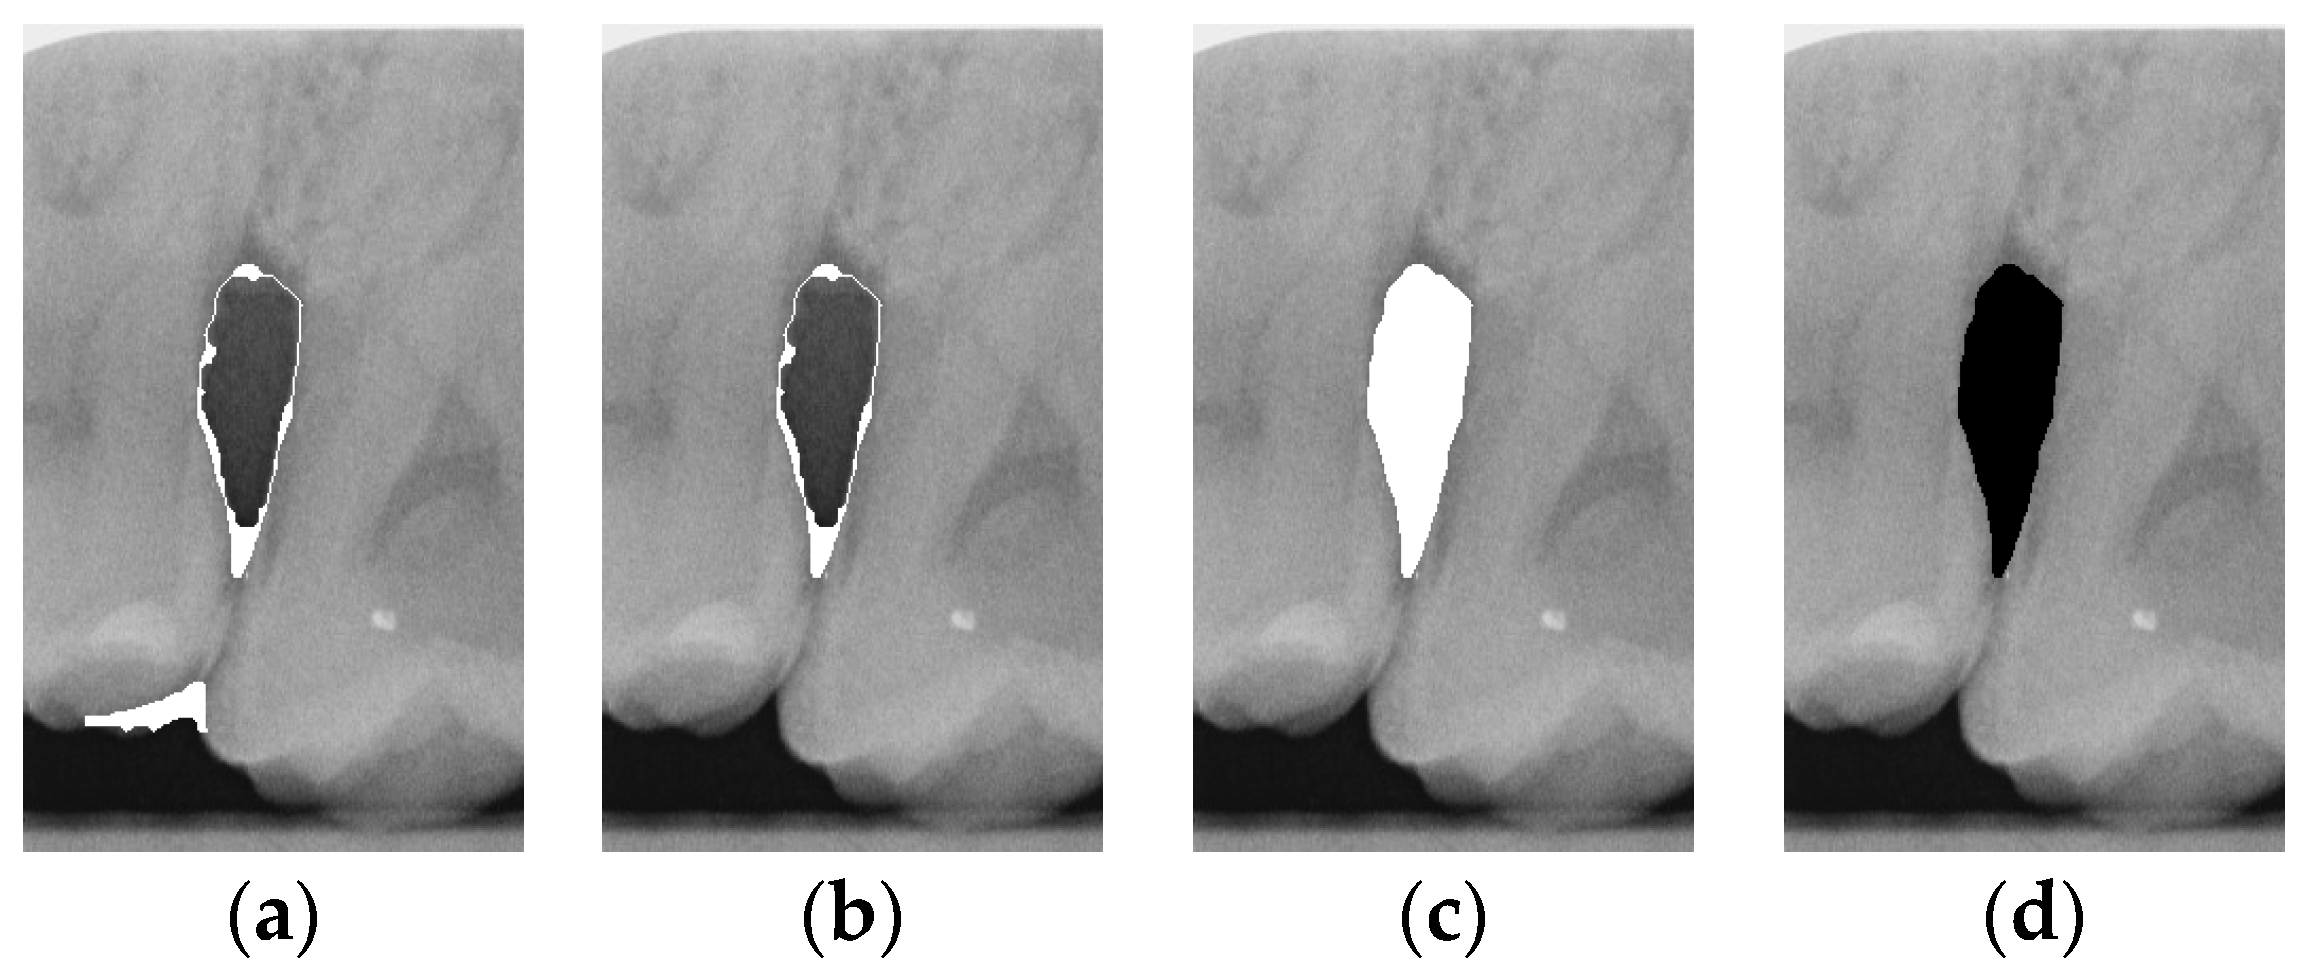

2.3.2. Adaptive Thresholding

Image thresholding is carried out to extract the object contours or regions in the image for subsequent image analysis and processing. For the filtered image, this involves making the image contours more obvious and masking the unwanted regions. The adaptive threshold binarization is shown in Figure 4b, and it determines the threshold of each pixel point based on the distribution of pixel values within its neighborhood. Usually, the size and shape of the neighborhood are adjustable to better accommodate different image characteristics. This study adopts adaptive thresholding to superimpose the white regions in binarization onto the original image by using the negative effect after the excess teeth are binarized using adaptive thresholding for subsequent image enhancement, as shown in Figure 4.

2.3.3. Enhancement of Mask

According to the above results, it is found that some images still have a few lines or color blocks in the non-symptomatic areas, which will affect the subsequent training of the model judgment. To solve this problem, the upper and lower 1/7 and the left and right 1/8 of the image are masked, which is the area where the symptoms are located; this is carried out not only to highlight the symptoms, but also to filter out the residual lines and color blocks in the non-symptomatic areas, which will be helpful for the subsequent steps. The result is shown in Figure 4d.

Figure 4. Comparison of thresholding images. (a) Original image. (b) Thresholding image. (c) The image applied to the original image by the negative effect. (d) Enhancement of Masked Image.